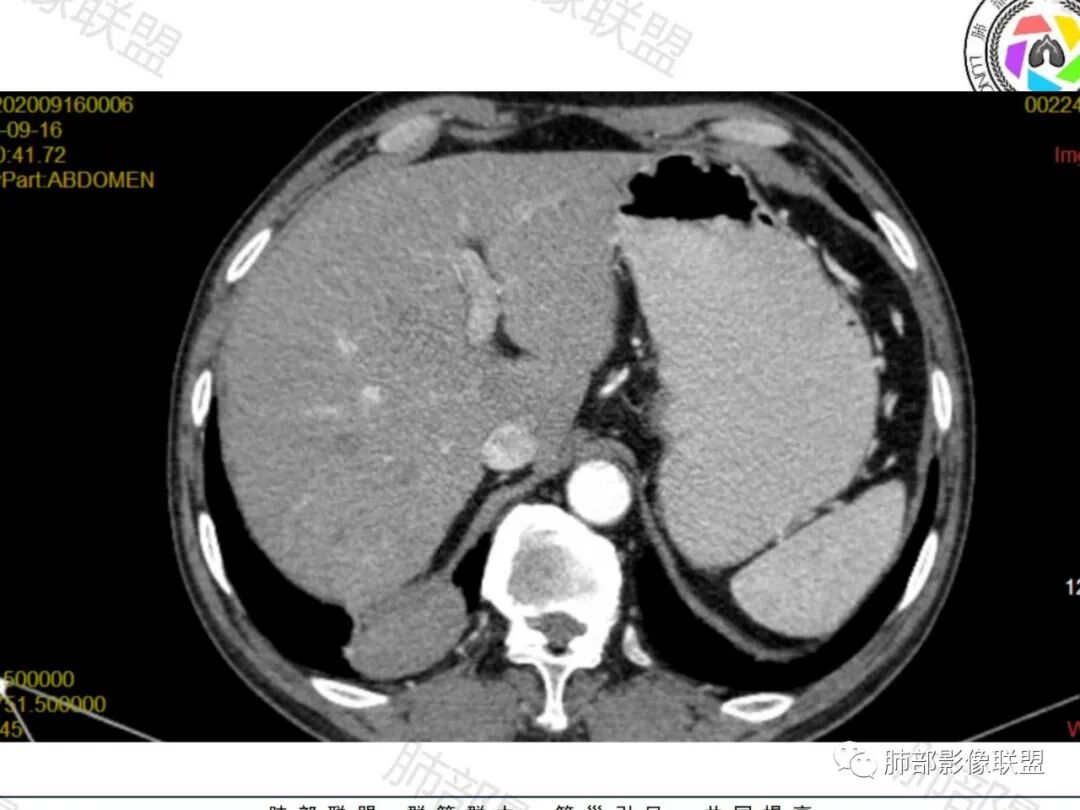

右肺下叶一类圆形肿块影,内缘边缘光滑,外缘边界模糊,可见磨玻璃影,整体以彭隆为主,部分边缘包绕支气管,平扫密度尚均匀,增强后不均匀强化,部分与膈肌黏连,临床,62岁男性,无症状,考虑恶性:腺癌,鳞癌,神经内分泌癌,肉瘤

男性,62,胆结石入院胸部CT偶然发现占位。肿标稍增高,右肺下叶胸膜下肿块,边缘尚清,密度较均匀,增强明显强化,血管贴边,空气新月征?静脉期可见低强化区,首先考虑PSP,鉴别肉瘤样癌及神经内分泌肿瘤

老年男性,肿瘤标志物高,右肺下叶类圆形肿块,宽基底与胸膜相连,边缘光整,密度均匀,周围气管及血管受压推移,延迟强化,其内见纤细血管,似有小低密度灶,首先考虑间叶组织恶性肿瘤,良性平滑肌瘤、纤维瘤不除外

患者中老年男性,检查发现右下肺占位。查肺癌标记物稍有升高。血常规白细胞计数稍降低。胸部CT:右肺下叶后基底段类圆形肿块,边缘光滑,边界清楚,周边见气管受压扩张,增强轻度强化,内见点状低密度影,见血管贴边。综合考虑良性过低度恶性病变,PSP可能,其它恶性肿瘤待排。

老年男性,检查发现右下肺占位。CT:右肺下叶一类圆形肿块影,膨隆,无分叶,边缘基本光滑,近端支气管推挤狭窄,与胸膜夹角为锐角,增强见不均匀强化,未见坏死,近端见血管贴边,胸壁脂肪间隙清楚。考虑良性病变——PSP可能性大。鉴别神经内分泌癌、肉瘤、SFT。

右肺下叶软组织肿块,边缘光滑,临近血管受压变形且增粗,增强后见斑片状低强化区,界不清,实性部分见条状血管影,边缘光滑,考虑PSP可能,肿块与支气管关系不密切,腺癌,腺鳞癌不符合,肿块内增强后血管走形自然,间叶组织起源肉瘤不符

右肺下叶肿块,呈外带大内带小的椭圆形改变(内带受支气管及血管挤压原因),边缘光滑,无分叶毛刺,支气管受压,增强后,均匀延迟强化,动脉期见血管贴边,静脉期内部瘤样血管强化区,相邻胸膜无侵犯,纵隔无淋巴结肿大,符合PSP,不鉴别。

胸部CT:右肺下叶一类圆形肿块影,边界清楚,大部分边缘光滑、外缘边界模糊,邻近支气管推移、血管贴边,病灶内可见分枝状血管,平扫密度尚均匀,增强后大部分均匀延迟强化,部分与膈肌黏连、尾征?考虑:类Ca>PSP>SFT。鉴别肉瘤样Ca,CD等。

肿块位于周围(起自细支气管呼吸道上皮),均匀膨胀生长(符合良性的生长特点),病灶内部大部分密度较均匀,部分小低密度不强化区(囊变),增强强化较明显,边缘血管增粗贴边,临近支气管受压,支持PSP。

常规肿瘤如果背侧胸膜来源,肿瘤与胸膜之间不应该夹杂含气支气管,会推移

但是肺内可以将支气管外推,夹在胸膜之间

与膈面胸膜类似推断

支持肺内

但是这条血管需要交代一下:

如果这是同一根肺动脉,支持PSP

因为肺门区来源肺动脉